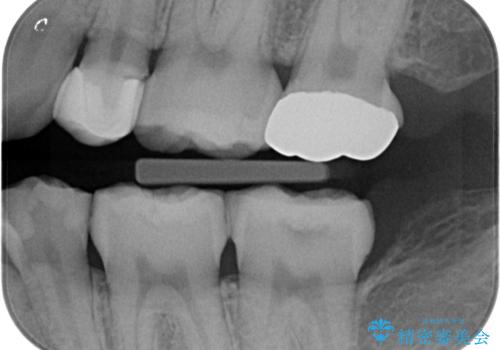

- 他院で被せた保険の白い被せ物(樹脂)をセラミックの被せ物に変えたいとの事で来院。

被せ物を外し、虫歯がないことを確認してセラミックの被せ物(ジルコニアクラウン)の治療を行いました。